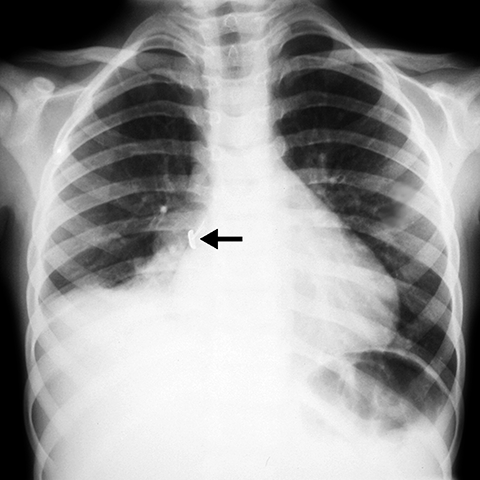

支气管异物Foreign body in Bronchus [1 of 3]